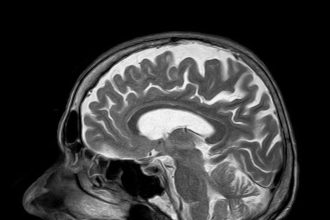

En sık duyduğum serzenişlerden birisi “Ama beyin MRG çektirmeden senin migrenin var dediniz!” Pekâlâ, bu serzenişler ya da bu algı…